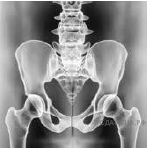

11. Какой сустав изображён на рентгеновских снимках?

Варианты ответов

- коленный

- тазобедренный

- голеностопный

- локтевой

12. Какие суставы человека изображены на рентгеновском снимке?

- тазобедренные

- коленные

- плечевые

- локтевые